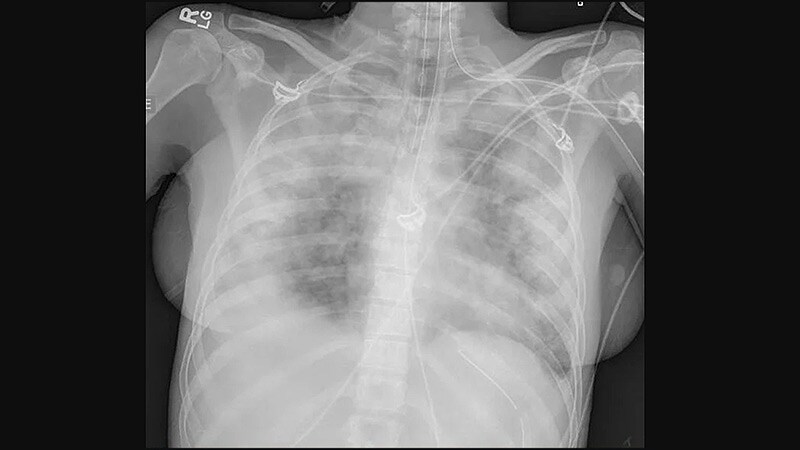

Pulmonary Medicine

Radiology